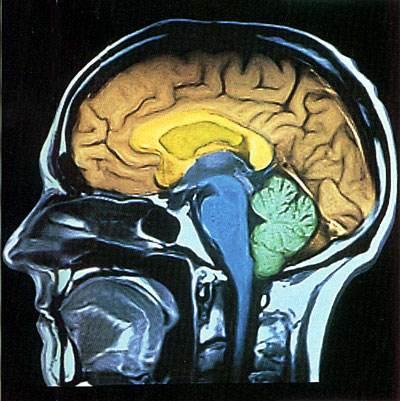

人类大脑十大未解之谜仅仅是人类对自身的迷惑 。 人类身体上很多的难解之谜是存在于我们大脑中的 。 大脑是一个让人感到迷惑的器官 , 尤其是在有关生与死、意识、睡眠、幻觉、记忆等问题 , 一直困惑着人们 , 让我们共同走进人类的大脑 , 一起探索人类大脑的未解之谜!